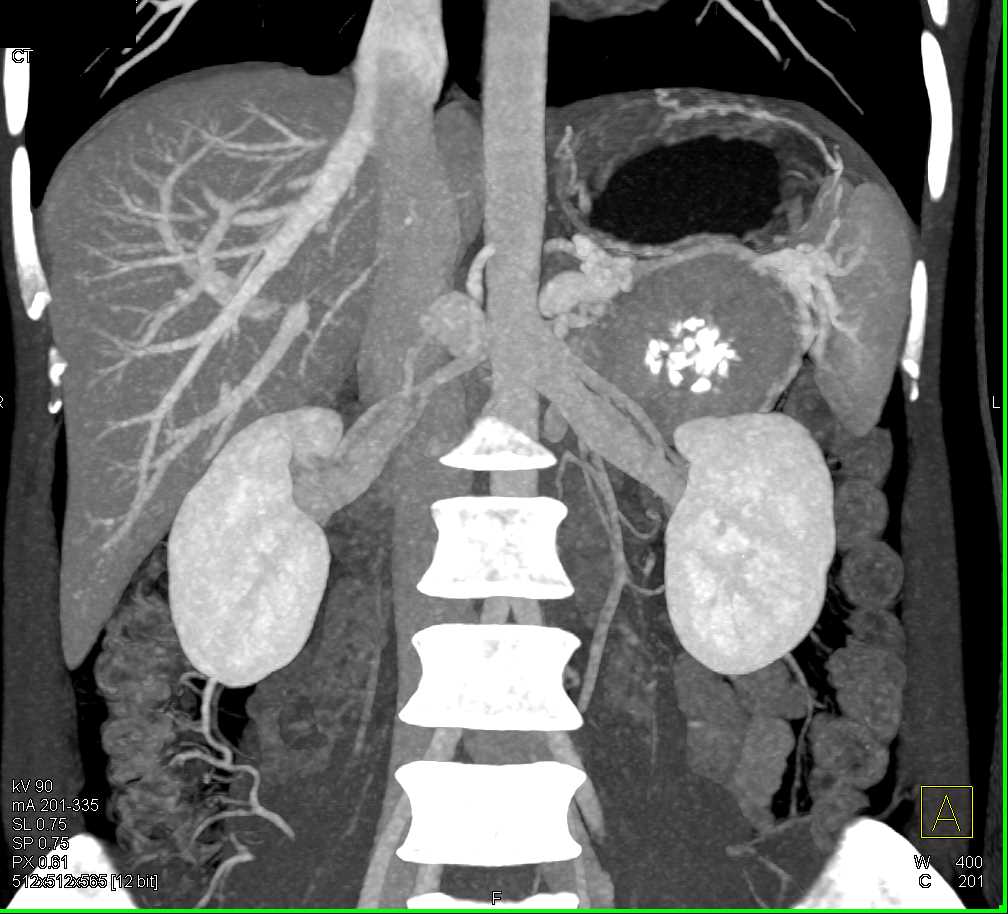

PNET Tail of the Pancreas